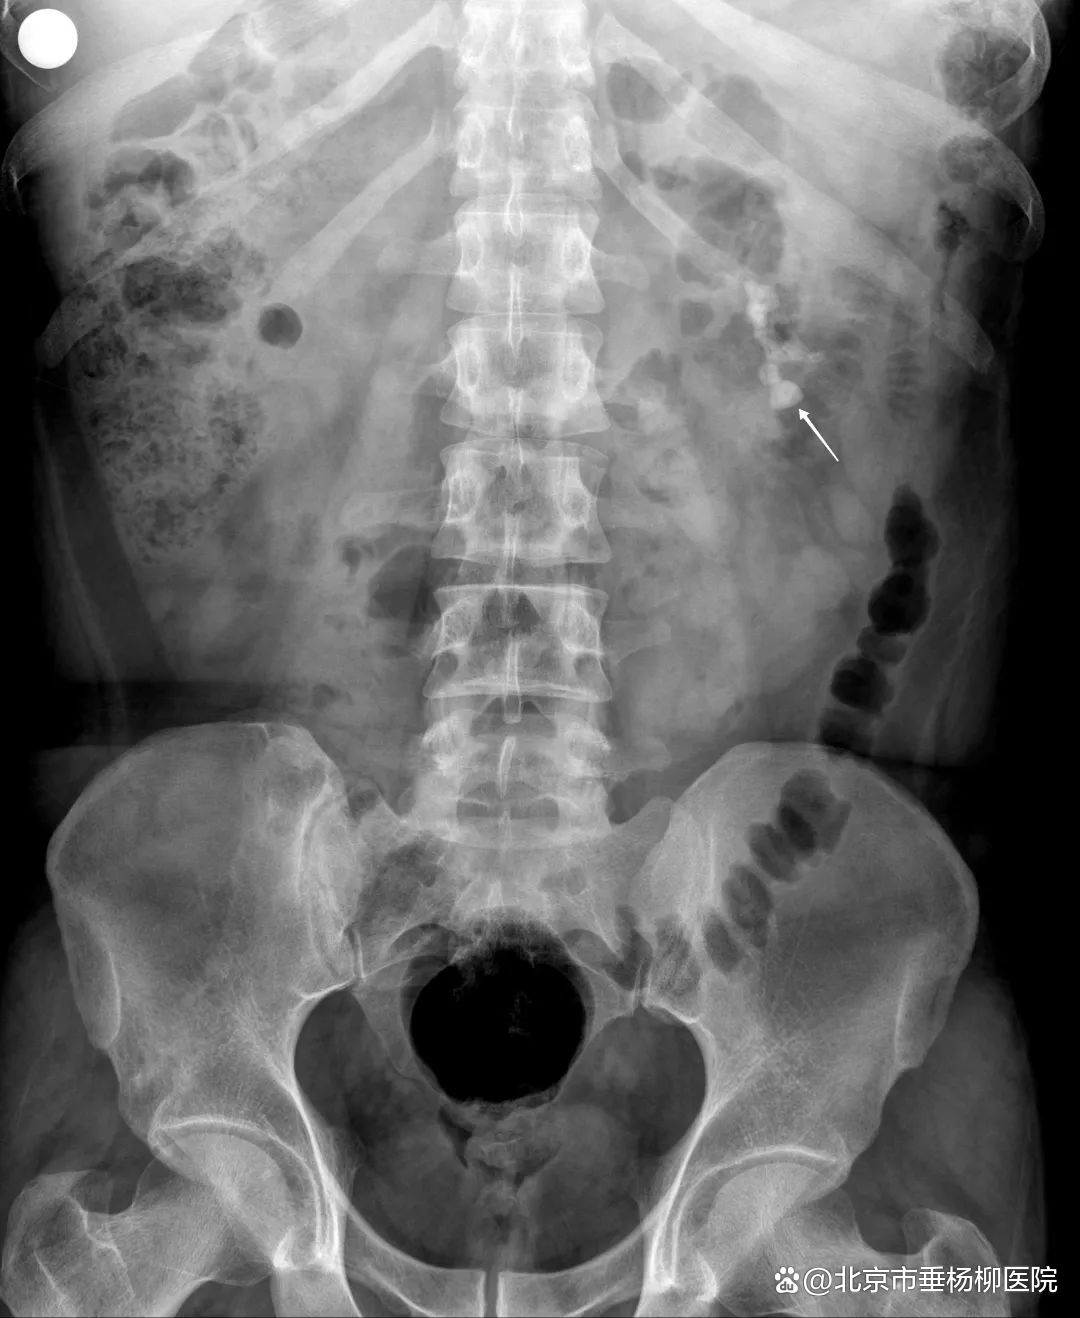

▲术后(结石消失)

1个月后,按照诊疗计划,泌尿外科团队再次成功完成了Ⅱ期左侧输尿管软镜钬激光碎石取石术。术后复查泌尿系平片提示左肾结石已全部粉碎。